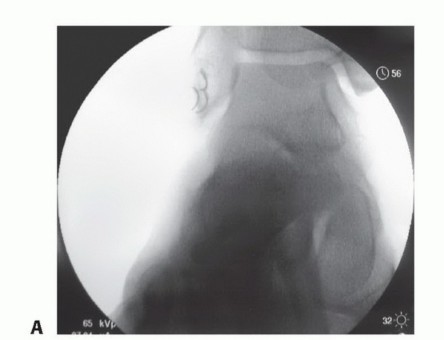

DEFINITION Trochlear dysplasia is a pathologic condition occurring in approximately 3% of the population but …